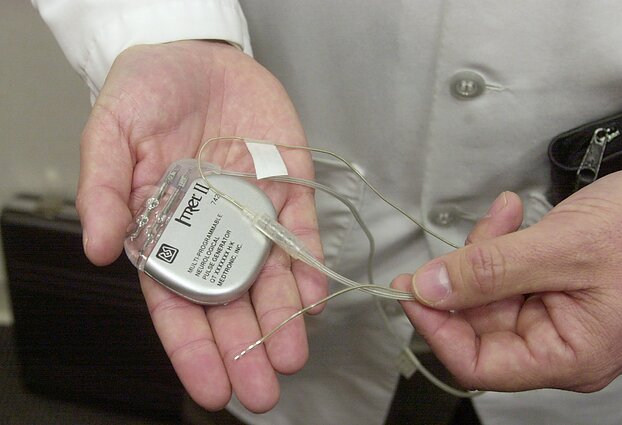

Esminis technologijos veikimo principas – sąsaja tarp smegenų ir kompiuterio. Aštuoni elektrodai registruoja elektrinį aktyvumą, kai žmogus įsivaizduoja judinantis ranką, tuomet signalai perduodami į kompiuterį, kuris juos iššifruoja ir panaudoja liepdamas ant paralyžiuotos rankos uždėtam egzoskeletui atlikti norimus judesius.

Monetos dydžio NEO įrenginys – minimaliai invazinis implantas. Jis įtvirtinamas kaukolėje, o aštuoni elektrodai ne integruojami į pačias smegenis, bet padedami ant jų dangalo vienoje galvos pusėje.